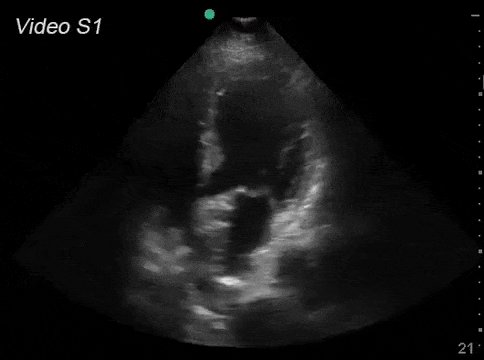

Takotsubo Cardiomyopathy

هو نادر ولكن يحدث وخاصة عند النساء في حالة الانهيار العاطفي الشديد بعد حدث إجتماعي جلل ...

من سماته توسع في النصف السفلي من البطين الأيسر ويؤدي إلى عجز مؤقت في وظائف القلب واحتقان الرئتين

سبب تسميته تاكوتسوبو أن في اليابان شبكة صيد الأخطبوط تسمى تاكوتسوبو وشبه المرض بها لان البطين الأيسر يتوسع في أسفله ويبقى أعلاه ضيق نسبيآ فيشبه شكل هذه الشبكه .....

النظريه السائده أن متلازمة Takotsubo أو متلازمة القلب المكسور ناتجه عن إفراز هرمون الأدرينالين من الجهاز العصبي بكميات تسوناميه تؤدي إلى عطل في عضلة البطين الأيسر وأحيانآ صدمه في الدوره الدمويه